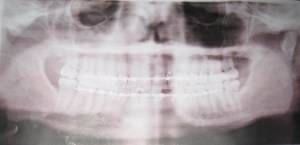

• Some time after I returned from my oral surgery, I found an x-ray of my mouth among the things that I had carried home from the surgeon’s office. I have never had any recollection of the taking of the x-ray, but it was apparently done after I had my mouth wired, as the wires are visible. Here it is. Note that the left side of my mouth (with the fracture) appears on the right side of the image.

x-ray

• It seems that I’ve neglected to explain that the part of my jaw that I broke, the condyle (or maybe it was the neck of the condyloid process, just below the condyle) is located near the joint with the upper jaw, rather than near the teeth. I suspect that this made the recovery easier than it otherwise might have been because the pictures of jaws broken between the teeth look far more gruesome than anything I saw on my own face.